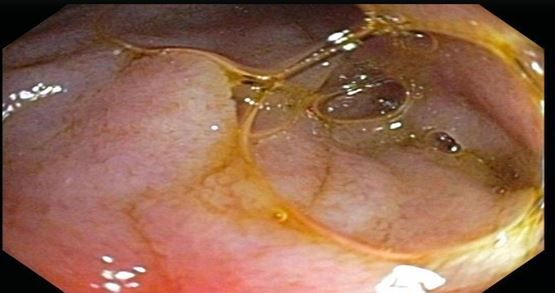

Figure 2. Luminal obliteration of third portion of the duodenum.

The next day, an esophagogastroduodenoscopy (EGD) was performed to rule out causes of obstruction. The study showed a hiatal hernia as well as luminal obliteration on the third part of the duodenum (Figure 2; click to enlarge) and visible pulsation. These signs are consistent with superior mesenteric artery (SMA) syndrome. A gastrojejunostomy was placed and enteral nutrition was initiated. The patient was able to tolerate tube feeds and was discharged with follow-up. At 8 weeks, the patient had gained sufficient weight and her symptoms had completely resolved.

Because the signs and symptoms of SMA syndrome can be nonspecific, radiographic evidence combined with a high index of suspicion can aid in diagnosis. Currently, an abdominal CT has proved most helpful in evaluating the aortomesenteric angle, the feature that has shown the most sensitivity for SMA syndrome.12 An EGD should also be performed to rule out other causes of obstruction. Although rare, one such classic finding is complete luminal obliteration of the distal duodenum with visible pulsation13-a sign consistent with SMA syndrome-which was seen in this patient. This further implicates the role of the mesenteric fat pads and spinal changes that can lead to SMA syndrome.